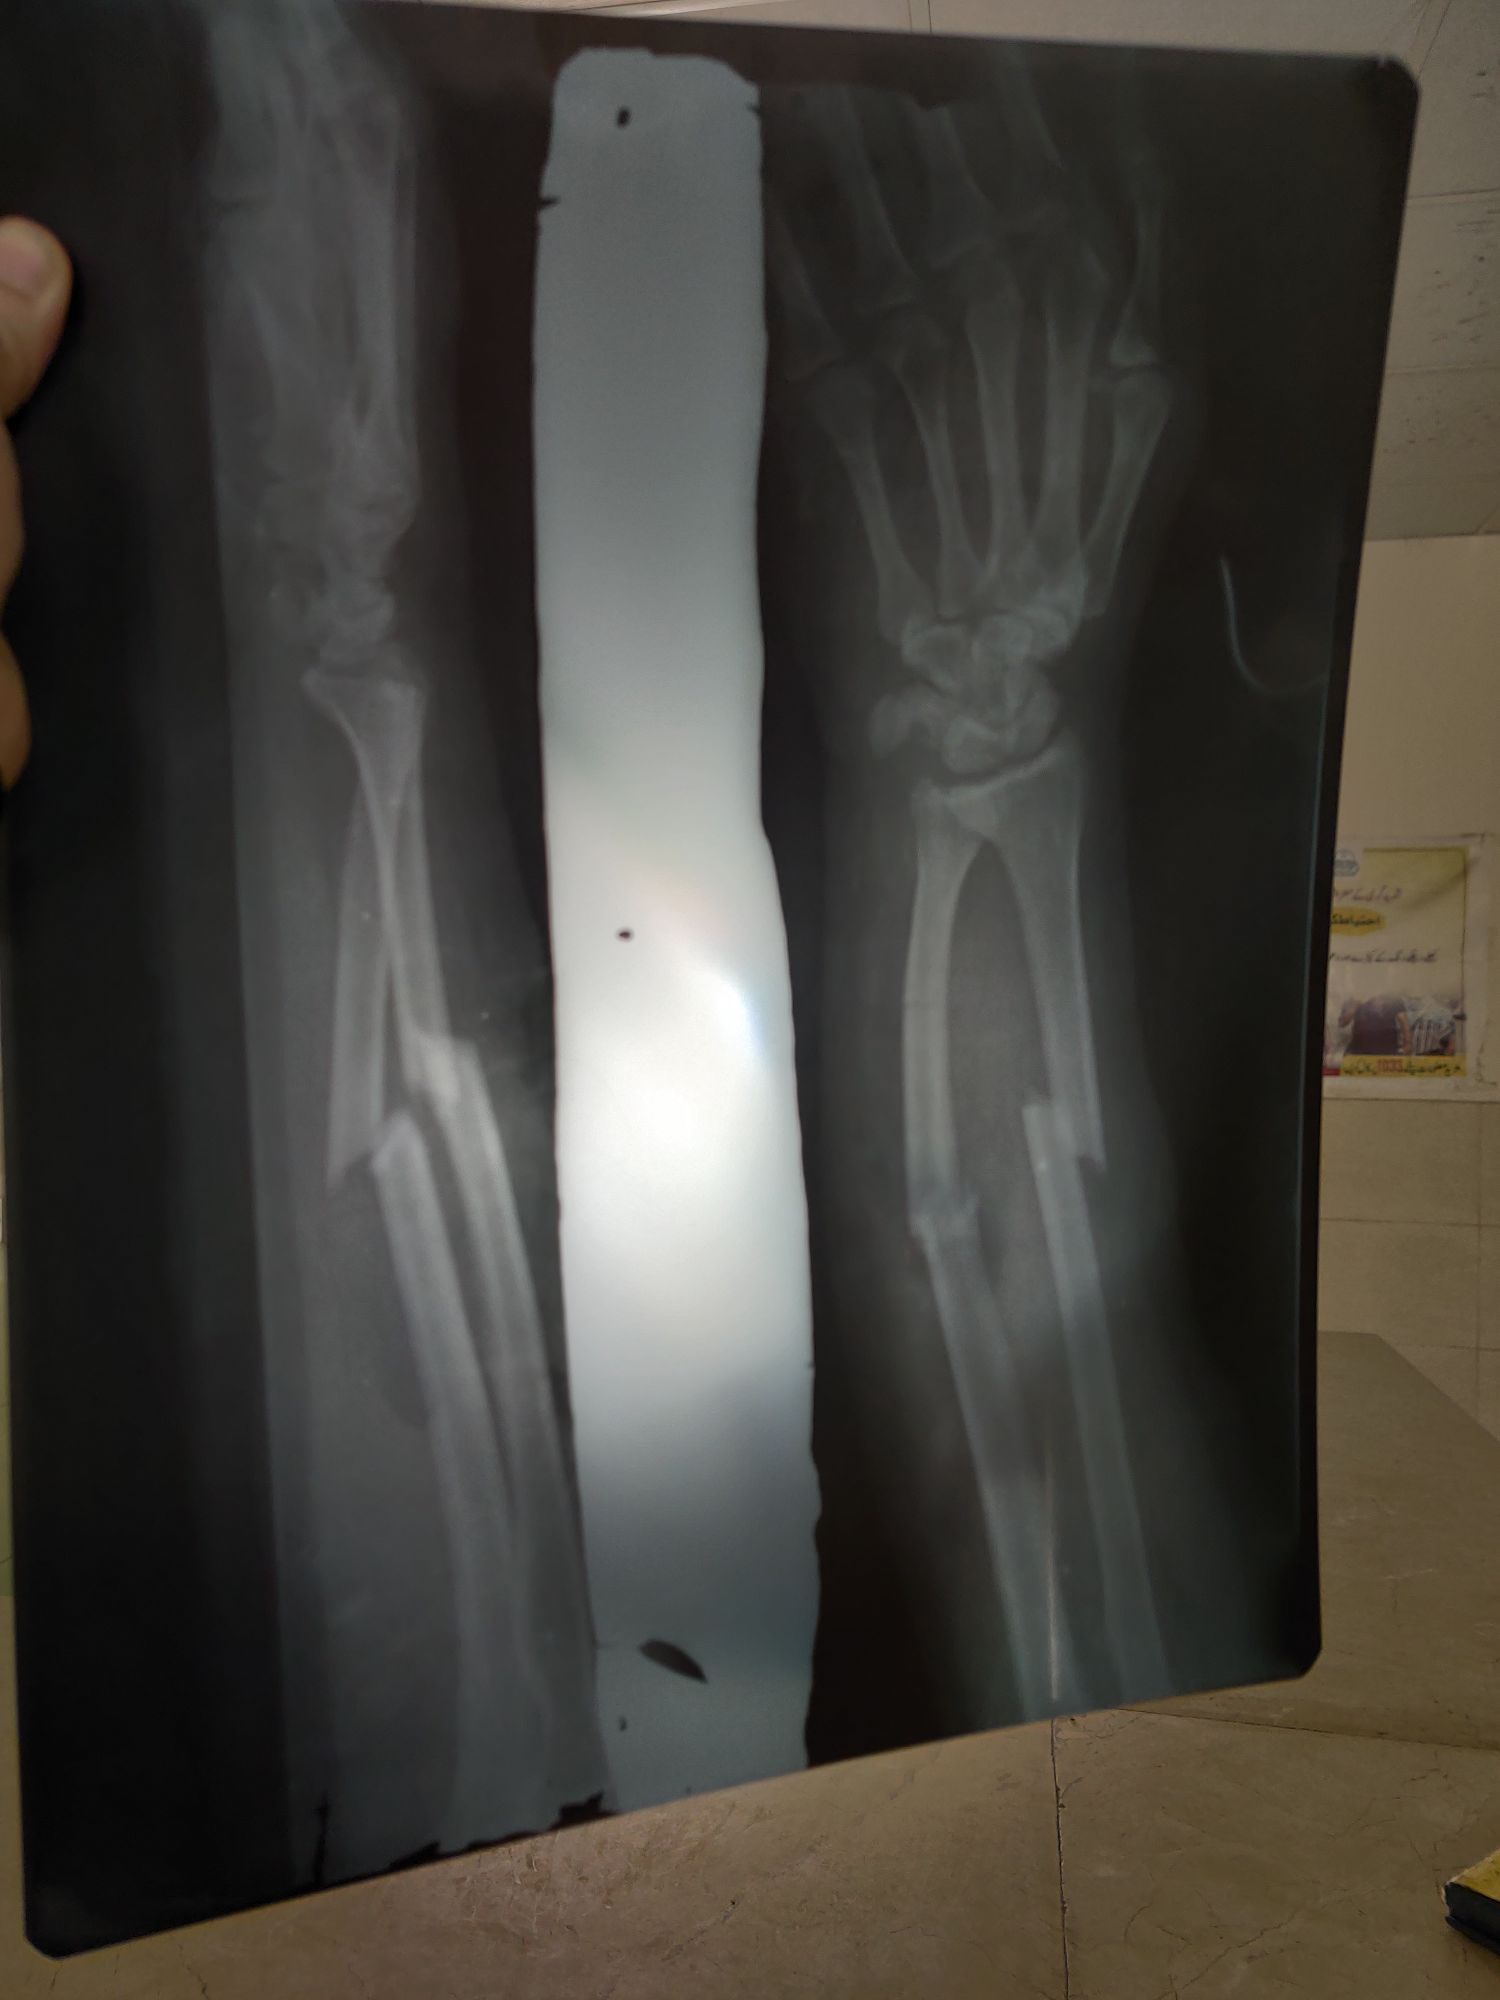

Radius + Ulna fracture

Radius

Rta

Ulna